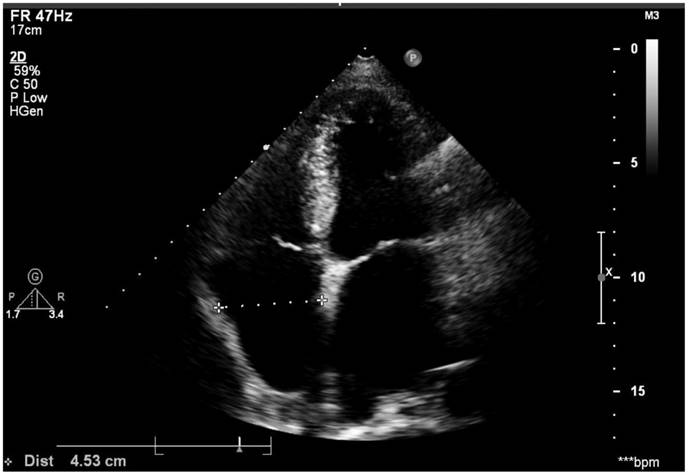

All the patients underwent trans-thoracic echocardiography (TTE) and trans-esophageal echocardiography (TEE) (Vivid, GE). The Left and right diameter was measured on the four-chamber apical view during systolic phase. The horizontal diameter of left atrium (LA) was determined as the measurement from the middle of mitral isthmus to the LA roof (endocardial surface), while the horizontal diameter of right atrium (RA) was determined as the measurement from the middle of tricuspid isthmus to the RA roof (endocardial surface), see Figure 1. LA and left atrial appendage (LAA) thrombus was excluded by TEE. Our standard techniques for echocardiography examination also included that all measurements were averaged from at least three cardiac cycles and then reviewed by two echocardiologists. Right atrium enlargement (RAE) was diagnosed from that the horizontal diameter of right atrium was above 40mm regardless of sex. Left atrium enlargement (LAE) was diagnosed that left atrium horizontal diameter was above 40mm for male and 35mm for female. Biatrial enlargement (BAE) was diagnosed when a patient was with both LAE and RAE. The normal value of echocardiography measurements in the Chinese population referred to the consensus statements endorsed by the Beijing Task Force on Echocardiography (13).

Figure 1

Right atrium diameter was measured using the four-chamber apical view during the systolic phase and left atrium diameter was measured also on this image.